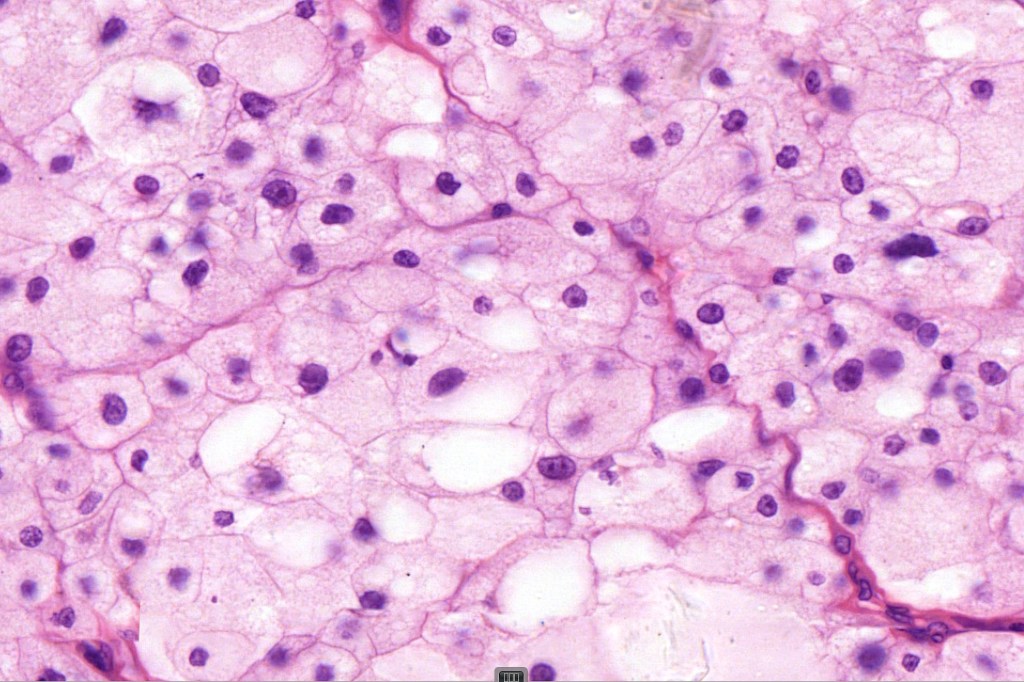

•Enlarged cells with copious eosinophilic, foamy or clear cytoplasm (some authors include melanoma with clear cell change in the same category)

•Variable pigmentation

•Nuclei vesicular or hyperchromatic

•Pleomorphism is not generally marked and indeed can be very subtle

•Variable mitotic activity

•DPAS granules

•Thought to be a result of abnormal or degenerative melanosome change